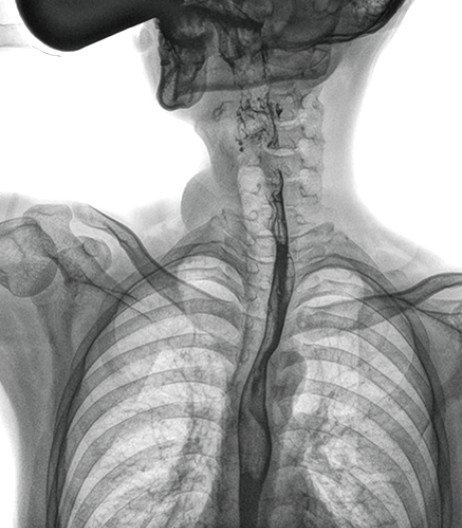

食管造影是食管病變的基本檢查方法,可以發(fā)現(xiàn)食管癌的特征性改變——食管粘膜的中斷和破壞,病人常感覺吞咽障礙,此特征在臨床中最常見,也是早期食管癌的典型表現(xiàn)。一般伴隨的特征有管壁充盈缺損、龕影、軟組織塊影、食管腔狹窄等;在透視下還可看到食管壁僵硬、蠕動(dòng)緩慢等。

動(dòng)態(tài)DR能夠?qū)崿F(xiàn)大幅面透視,瞬時(shí)高清點(diǎn)片等。在食管造影檢查中,由于吞咽鋇劑后,造影劑流速非???,在一個(gè)大幅面上方便觀察食管的病變。瞬時(shí)點(diǎn)片,可以實(shí)時(shí)捕捉到病變部位的影像,從而可以快速做出診斷。普利德多功能動(dòng)態(tài)DR擁有17×17英寸超大視野,一次曝光即可顯示整個(gè)食管,更方便觀察食管的病變,確定病變的范圍,對(duì)診斷和治療有重要參考價(jià)值。

與過去的數(shù)字胃腸機(jī)比較,動(dòng)態(tài)DR圖像分辨率高,對(duì)食管的全景觀察,局部粘膜破壞、中斷,管腔狹窄以及病灶范圍的顯示清晰度明顯更優(yōu)。

上消化道造影高清圖像

由此不難看出,動(dòng)態(tài)DR在食管造影的臨床應(yīng)用上,相比于其他檢查手段,成像清晰、應(yīng)用便捷,而且能夠充分顯示食管的局部和整體結(jié)構(gòu)形態(tài),并以此揭示相關(guān)形態(tài)和功能性改變,更有利于助力實(shí)現(xiàn)精準(zhǔn)診斷。